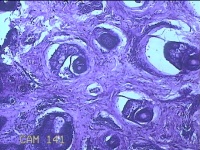

性别

男

年龄

23岁

临床诊断

右耳部肿物

一般病史

右耳前无痛性肿物20余年。

标本名称

大体所见

灰白暗红色肿物0.7x1.5x0.2cm一个,表面糜烂。

组织没固定好